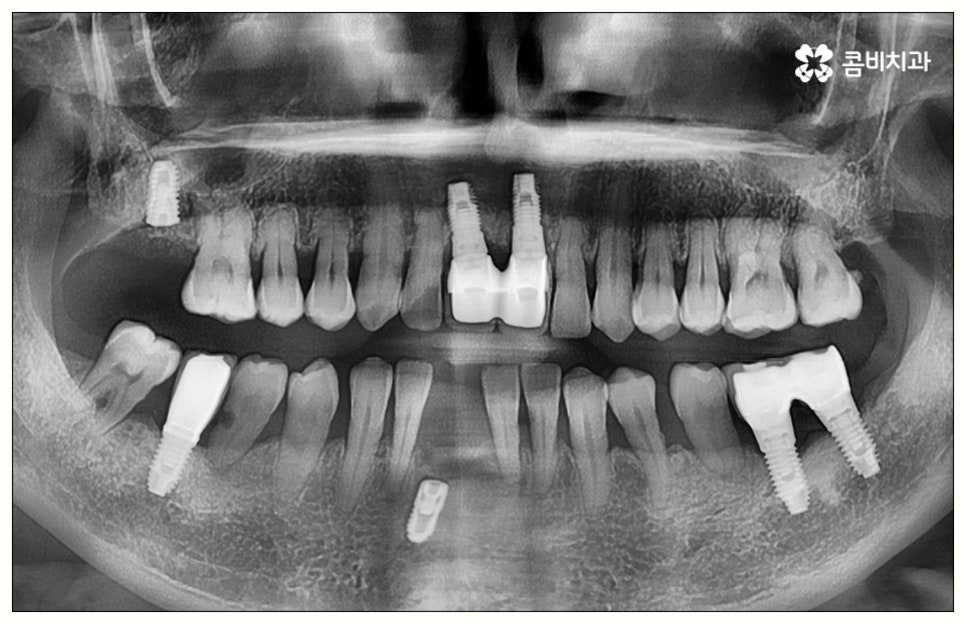

특히 임플란트 기술의 꽃이라고 할 수 있는 원데이임플란트 방식을 이용하면 발치부터 식립, 임시치아 장착까지 하루 만에 가능하기 때문에 비교적 긴 치료 기간이나 잦은 내원에 따른 어려움, 통증에 대한 두려움 등 환자분들이 느끼는 여러가지 부담을 많이 줄여줄 수 있어요. 치아 상실과 동시에 원데이임플란트 시술을 받으면 치아 공백 기간을 줄여 치조골이 위축되는 것을 방지해 주어 뼈 보존 측면에서도 유리하며, 특히 앞니와 같이 입을 벌렸을 때 잘 보이는 위치에 있는 치아를 상실한 경우 원데이임플란트 를 이용하면 빠른 수복이 가능하기 때문에 일상 생활에서 겪는 불편이 크게 감소할 거예요.

그러나 모든 환자분들이 원데이임플란트 방식을 이용할 수 있는 것은 아니기 때문에 주의하실 필요가 있어요. 말씀드렸던 것처럼 임플란트 수술은 직접 환자의 잇몸뼈에 식립을 진행하는 방식의 치료이기 때문에 잇몸뼈 상태가 양호하지 않은 분들의 경우 발치 후 바로 임플란트를 심는 것이 식립 성공률이나 지속적인 안정성 측면에서 좋지 않을 수 있어요. 특히 잇몸 질환으로 인해 염증이 심한 경우 또는 바탕이 되는 잇몸뼈의 밀도나 높이가 많이 부족한 경우에는 원데이임플란트 방식이 불가능하다고 할 수 있는데요.

이때 만약 무리하게 즉시 식립을 진행하게 되면 임플란트 치아가 제대로 기능하기 어려울 뿐 아니라 주위염 등 부작용을 일으킬 가능성이 높아 주변 잇몸 및 치아에도 좋지 않은 영향을 주게 되며 결국 임플란트가 흔들리거나 빠지면서 재수술이 필요한 상황까지 이를 수 있으므로 필요한 치료부터 선행하는 것이 좋을 거예요. 위에서 예로 든 상황이라면 잇몸 염증을 먼저 꼼꼼하게 치료한 후 또는 뼈이식술을 통해 안정성을 높인 후에 임플란트 식립을 진행하실 필요가 있어요. 이 과정에서 무엇보다 중요한 것은 수술 전 3D CT를 통해 환자의 상태를 정확하고 꼼꼼하게 확인하고, 환자의 연령, 치아를 상실하게 된 원인 및 시기, 식습관 등 관련된 모든 부분을 빠짐없이 검토하여 각자에게 꼭 맞는 계획을 세운 다음 회복 정도를 체크해 가면서 무리하지 않게 진행해 나가는 것이기 때문에 정밀 진단 장비 및 숙련된 의료진이 있는 치과에서 임플란트 치료를 받으시도록 권유드리고 있습니다.